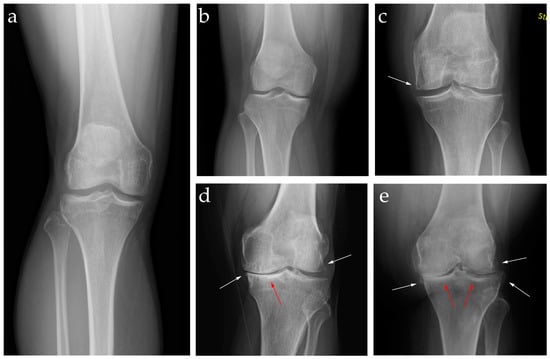

2.2. Diagnosis: Clinical Features and Image Findings